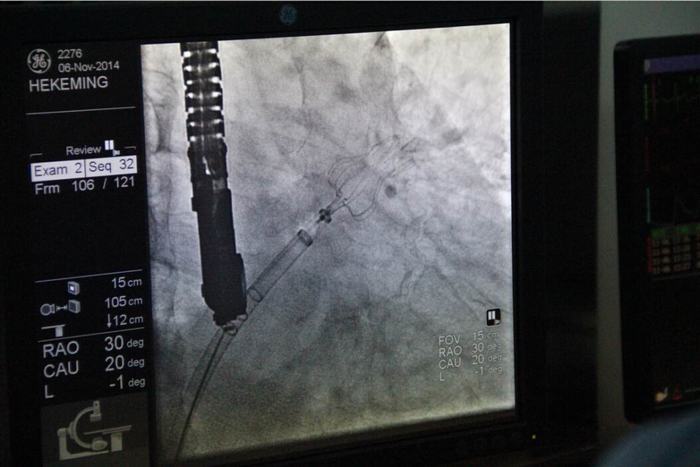

2014年11月6日在我院董事會(huì)、院領(lǐng)導(dǎo)及心血管病醫(yī)院各級(jí)領(lǐng)導(dǎo)的大力支持下,由德籍華人李教授及兩名美國(guó)專家的協(xié)助,心血管病醫(yī)院張玉順院長(zhǎng)親自手術(shù),在心臟導(dǎo)管室、外科手術(shù)室及B超室醫(yī)護(hù)人員的全力配合下,經(jīng)過(guò)一小時(shí)緊張而有序的工作,順利完成了西北地區(qū)首例“左心耳封堵術(shù)”。此手術(shù)創(chuàng)傷小,痛苦少,恢復(fù)快,預(yù)后好。為目前根治房顫導(dǎo)致中風(fēng)最先進(jìn)及可靠的方法,避免了長(zhǎng)期服藥的副作用,減輕了患者的經(jīng)濟(jì)負(fù)擔(dān)。該項(xiàng)技術(shù)國(guó)際領(lǐng)先,國(guó)內(nèi)剛剛引進(jìn)。此手術(shù)的順利開展預(yù)示著我院醫(yī)療診治及介入手術(shù)水平已跨入國(guó)內(nèi)先進(jìn)行列,與國(guó)際接軌,填補(bǔ)了西北地區(qū)空白,為廣大患者帶來(lái)福音。